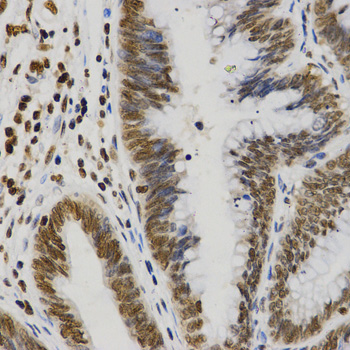

Immunohistochemistry of paraffin-embedded human rectal cancer tissue using H3R8me2s antibody at dilution of 1:200 (x400 lens).